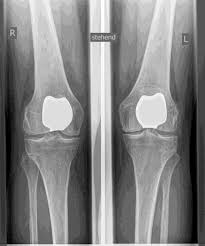

Man spricht bei künstlichen Kniegelenken von Vollprothesen und Teilprothesen. Welche Prothese für Sie in Betracht kommt, Prüfe ich sorgfältig vorher anhand der klinischen Untersuchung, sowie anhand von Röntgenbildern oder MRT-Aufnahmen.

- zementierter Vollständiger Oberflächenersatz (Klassisch: die "Knie-Prothese")

Das künstliche Kniegelenk ersetzt die durch die Arthrose zerstörte Knorpeloberfläche. Der darunterliegende Knochen am Oberschenkel und Schienbeinkopf bleibt erhalten. Manche vergleichen ein modernes künstliches Kniegelenk mit einer

Überkronung bei einem Zahn, der genaue Begriff ist der sogenannte

bikondyläre Oberflächenersatz. Zwischen den neuen Oberflächen am Ober- und Unterschenkel befindet sich das sogenannte Inlay aus einem speziell verhärteten weißen Kunststoff, das im Röntgenbild als Abstand zwischen den Metallteilen zu erkennen ist.